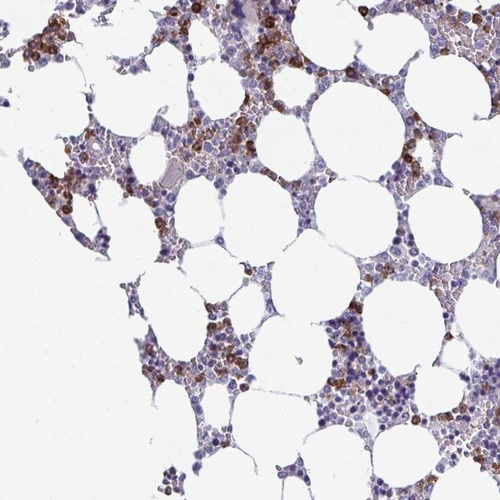

Immunohistochemical staining of human bone marrow shows strong cytoplasmic positivity in subset of hematopoietic cells.